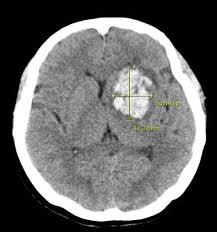

뇌출혈 수술은 뇌혈관이 파열돼 뇌 안에 피가 고인 상태를 제거하거나 압박을 완화하는 수술로, 이후 **의식회복 여부는 환자 예후를 결정하는 핵심 요소**입니다. 회복은 개인의 상태, 출혈 부위와 범위, 나이, 기저질환 등에 따라 크게 차이가 있으며, 적절한 치료와 재활, 가족의 지지가 매우 중요합니다.

- 출혈의 크기와 위치: 뇌간·기저핵 출혈은 의식회복 가능성이 낮음